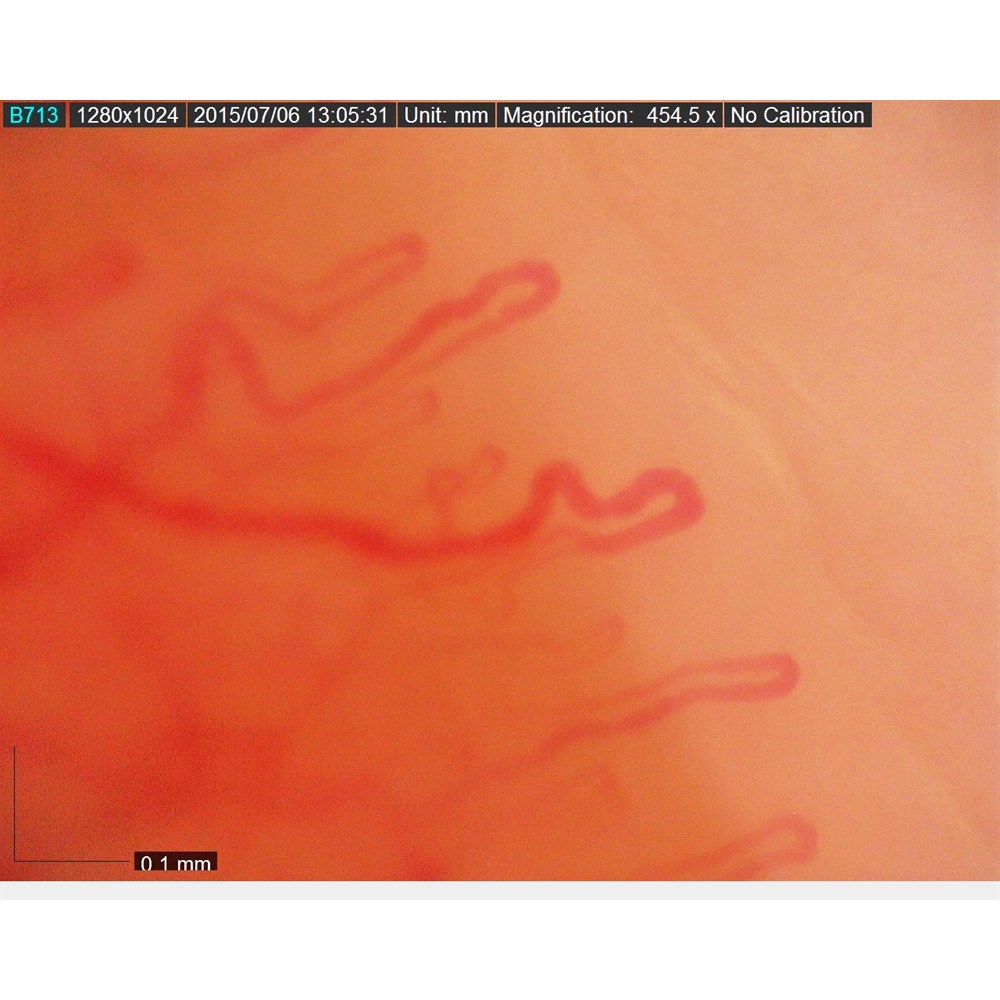

CapillaryScope 500 Pro (MEDL4N5 Pro) benytter den nyeste, avanserte optikken og tilbyr førsteklasses bildekvalitet og fargegjengivelse i et robust og kompakt hus. Med dette kompakte og allsidige digitale CapillaryScope er det svært enkelt å ta og lagre svært detaljerte bilder av neglefoldkapillaroskopi med en høy forstørrelse på 500×.